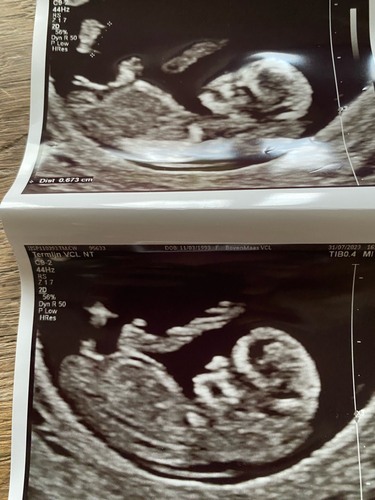

Heeft iemand een idee? Wij denken een meisje. Foto 1

Foto 2

Girl! 💗